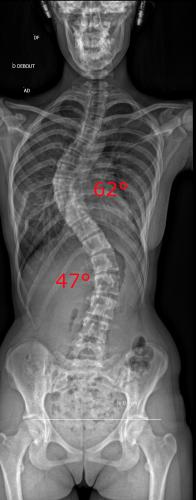

Images de scolioses opérées 16 janvier 202418 janvier 2023 par Damien Scoliose Thoracique et lombaire 1 Radio pré-opératoire de Face Radio pré-opératoire de Profil Radio à 1 an de recul de Face Radio à 1 an de recul de Profil